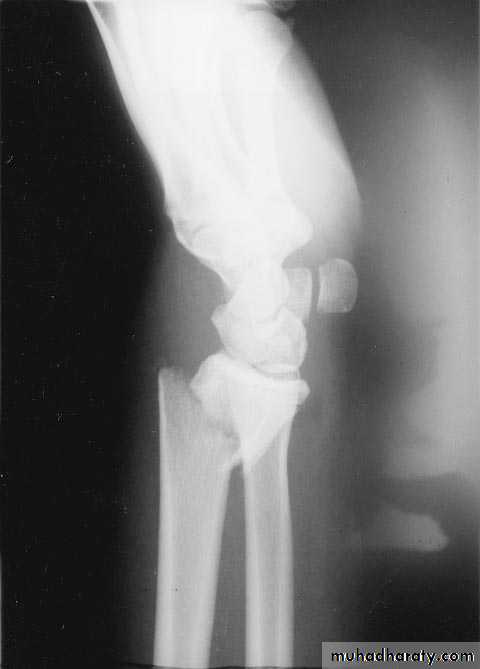

Smith fracture :it is the same as colles` fracture but the distal segment is displaced anteriorly .

It is intra articular fracture of the lower end of the radius with subluxation of the wrist joint.It is of two types :

1- volar Barton's`: called true Barton fracture and it associated with volar subluxation of the carpus . The fracture line run obliquely across the volar lip of the radius into the wrist joint . The distal segment displaced anteriorly carrying the carpus with it .

Treatment : the fracture easily reduced but it is unstable so it can easily redisplaced so the treatment will be by open reduction and fixation by special plate called Buttress plate .

2- dorsal Barton`s: it is the reverse of the volar one .